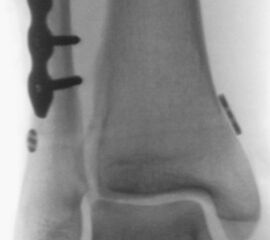

Gardner et al. konnten beispielsweise zeigen, dass die offene anatomische Reposition der Tibiahinterkante der Stabilisierung mittels Stellschraube überlegen war und gleichzeitig mit einer geringeren Rate an postoperativen Fehlstellungen der Fibula in der CT-Kontrolle einherging 2728. Aus Sicht der Autoren ist prinzipiell die Stabilisierung über eine direkte Reposition indiziert, wenn die Größe des Fragmentes dies erlaubt. Bei gleichzeitigem Vorliegen einer Fraktur des lateralen und/oder medialen Malleolus sollte zunächst die Versorgung der des Tibiahinterkantenfragments erfolgen. Dies erlaubt die radiologische Kontrolle der Reposition und Osteosynthese-Lage, welche durch eine zuvor aufgebrachte Fibula-Platte häufig erschwert ist 29. Dafür werden die Patienten in Seitenlage gelagert. Dies erlaubt die direkte Versorgung der posterioren Malleolusfraktur über einen posterolateralen Zugang 30. Das sehr kräftige Periost wird im Frakturverlauf inzidiert und aus den Frakturspalt entfernt, so kann eine anatomische Reposition erfolgen. Entsprechend der Fragmentgröße erfolgt entweder die Versorgung mittels Drittelrohrplatte in Antiglide-Technik oder eine Zugschraubenosteosynthese. Die Versorgung der Fibula-Fraktur gelingt über den gleichen Zugang. Zur Versorgung des medialen Malleolus wird der Patient auf den Rücken umgelagert. Dies kann bei entsprechender Vorbereitung ohne erneutes steriles Abdecken erfolgen. Durch dieses Vorgehen konnte im eigenen Kollektiv die Notwendigkeit einer Stabilisierung der Syndesmose mit Stellschraube/Tight Rope deutlich reduziert werden.